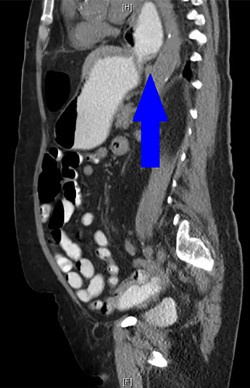

During the hospitalization, initial cardiac workup with 12-lead electrocardiogram and serial troponins was negative. The patient’s oncologic medications were held without improvement of the pain as well as to prevent leukopenia and neutropenia, if surgery was indicated. Palliative care was unable to achieve adequate pain control with oral and IV medications, and the patient did not want to pursue hospice care. Surgical consultation was obtained, and further evaluation with a CT scan of the chest, abdomen and pelvis with oral and IV contrast demonstrated an anteromedial diaphragmatic defect through which a prominent amount of mesenteric fat and a portion of the colon herniated representing a Morgagni hernia (Figs. 1–4). An increase in the size of the previously known PEH as well as the Morgagni hernia was noted. Due to continued chest pain unrelieved by opioids, a joint decision was made between surgeon, oncologist and the patient to proceed with surgery. She underwent successful robotic laparoscopic repair of the Morgagni hernia and PEH with dulex mesh for reinforcement. Her chest pain subsequently resolved. The patient gradually tolerated oral feeds and was eventually discharged in stable condition.

A CT abdomen and pelvis with oral contrast from 2015 demonstrates the presence of a PEH, identified by the blue arrow.